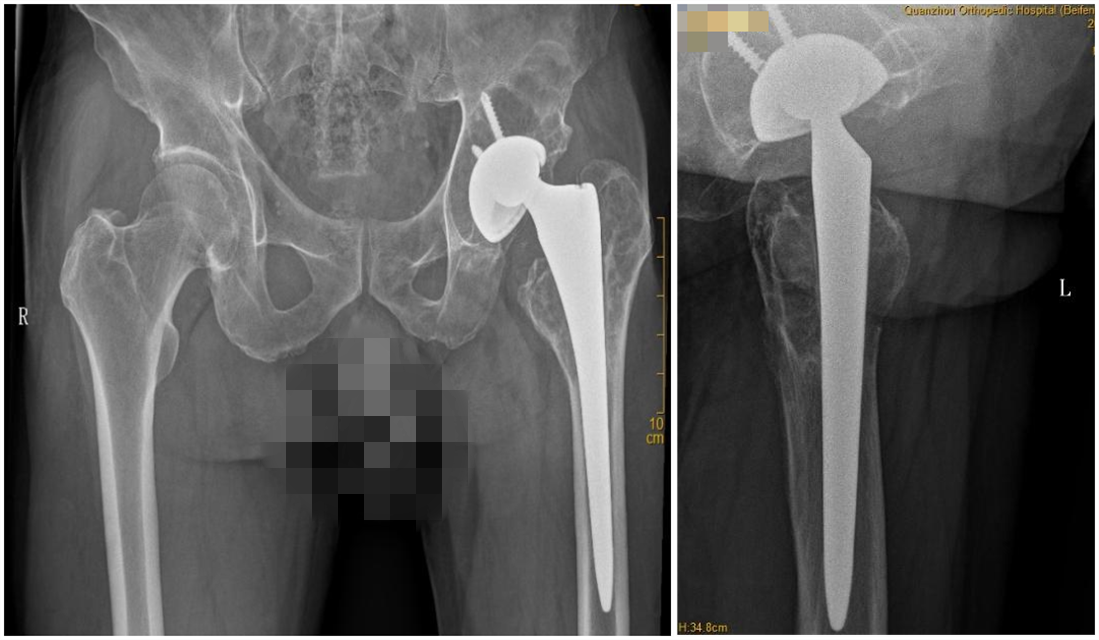

本报特邀泉州市正骨医院关节科科主任吴昭克副院长 本报记者张鸿鹏文/图通讯员黄玲艳 短短不到两个月,家住泉州安溪的林美花(化名)就做了两次髋关节人工置换手术。8月3日,在...